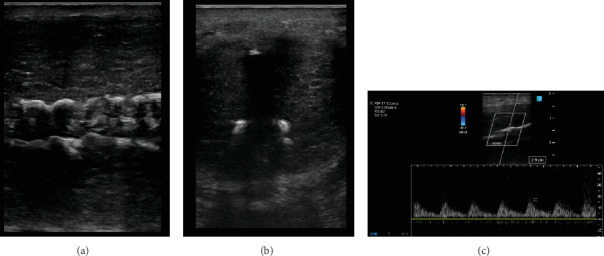

COVID-19大流行影响了全球数百万人。虽然主要被认为是一个呼吸过程,但可能有直接和间接的泌尿系统后果,但很少讨论。本病例报告描述了一例严重感染COVID-19导致肾和肝移植的患者。康复后,患者被发现有新发勃起功能障碍和佩罗尼病。我们怀疑导致肝肾功能衰竭的全身炎症和血管病变也导致了严重的动脉粥样硬化性勃起功能障碍。此外,俯卧位可能代表了Peyronie病的医源性病因。这个独特的病例表明,在照顾严重感染COVID-19的患者时,从男性健康的角度考虑了一些重要的问题。

The COVID-19 pandemic affected millions worldwide. While mainly regarded as a respiratory process, there may be both direct and indirect urologic consequences that are sparsely discussed. This case report describes a patient with a severe COVID-19 infection resulting in a kidney and liver transplant. After recovery, the patient was found to have de novo erectile dysfunction and Peyronie's disease. We suspect the systemic inflammation and vasculopathy leading to liver and renal failure also caused severe atherosclerotic erectile dysfunction. Furthermore, the prone positioning likely represents an iatrogenic etiology of Peyronie's disease. This unique case demonstrates some important considerations from a men's health perspective when caring for patients following a severe COVID-19 infection.